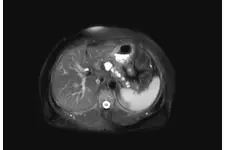

Tanı Yöntemleri Yenidoğanda kistik fibrozis tanısı koymak için birkaç yöntem kullanılmaktadır: